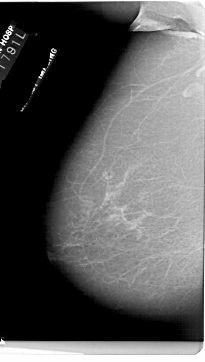

A_1727_1.LEFT_MLO

LEFT_MLO LINES 6871 PIXELS_PER_LINE 3886 BITS_PER_PIXEL 12 RESOLUTION 43.5 NON_OVERLAY